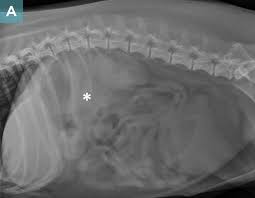

During physical examination of the dog, the vet may be able to palpate the tumour. Diagnosis of pancreatic cancer (insulinoma) in dogs diagnosis of insulinoma often begins after the dog has exhibited several symptoms consistent with the disease. Mind you, these dogs are very ill and mortality rates are also high. By then, it's too advanced to respond to treatment so the only thing a vet can do is try to manage the dog's pain, says the national canine cancer foundation. Symptoms include a mass on the gums, bleeding, odor, or difficulty eating. Pancreatic cancer in dogs is typically discovered when the disease is already in an advanced stage. Physical collapse, loss of consciousness seizures, and extreme weakness are common but because the insulin is released periodically, symptoms are not consistent. Usually a final diagnosis for both types is reached via an exploratory laparotomy. Your veterinarian will also perform abdominal radiographs in order to determine the presence of any masses or changes in the pancreas tissue. Since the symptoms are closely related to other ailments too, it is strictly recommended to take your dog to the wet. If imaging studies detect a mass in the pancreas, a pancreatic cancer diagnosis is likely, but not definite. Both tumors are more common in dogs than cats. Life expectancy unfortunately, the outlook for dogs diagnosed with stomach cancer is poor.

The pancreas is an internal organ that helps in the food digestion and regulates the blood glucose. Your veterinarian will also perform abdominal radiographs in order to determine the presence of any masses or changes in the pancreas tissue. Diagnosing pancreatic cancer in dogs is very difficult due to the late onset of clinical signs and that it can be confused with other conditions such as pancreatic nodular hyperplasia. Cancer may also develop inside the nose of dogs. Most dogs live for approximately 6 months after a diagnosis of stomach cancer. By then, it's too advanced to respond to treatment so the only thing a vet can do is try to manage the dog's pain, says the national canine cancer foundation. Diagnosis of pancreatic cancer in dogs your vet will likely try to see if he or she can feel a protruding mass in the abdomen, which can be a symptom of adenocarcinomas in the pancreas. He'll be looking for low levels of blood sugar, combined with anemia, increased white blood cells counts, and increased levels of bilirubin in the blood. Both tumors are more common in dogs than cats. Physical collapse, loss of consciousness seizures, and extreme weakness are common but because the insulin is released periodically, symptoms are not consistent. Pancreatic cancer pancreatic cancer is often hard to detect until the condition is at advanced stages, which is why the prognosis for dogs with this type of cancer is usually dire. When dealing with a pancreatic tumor in dogs, there are four main types: Large breed dogs and siamese cats may be predisposed.